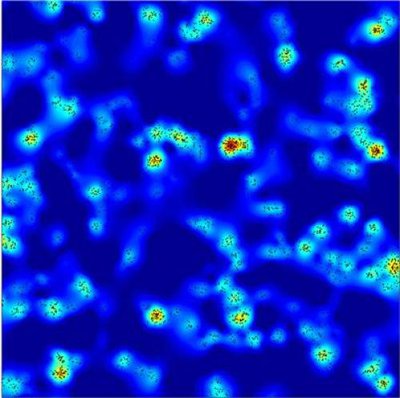

دانشمندان دانشگاه منچستر از تصاویر جدیدی رونمایی کردهاند که واضحترین تصویر تاکنون از چگونگی حمله سلولهای ایمنی سفید خون به عفونتهای ویروسی و تومورها را نمایش دادهاند.

به گزارش سرویس علمی خبرگزاری دانشجویان ایران(ایسنا)، این تصاویر نشان دادهاند که چگونه این سلولها که مسئولیت مقابله با عفونتها و سرطان را در بدن انسان بر عهده داشته، چیدمان مولکولهای سطحی خود را در زمان فعالسازی توسط پروتئین موجود در سلولهای تومور یا عفونت ویروسی تغییر میدهند.

از دیگر کشفیات مهم این پژوهش آن است که پروتئینهای موجود در سطح سلولهای ایمنی با فاصله برابر با هم قرار نداشته بلکه به شکل خوشهای گروهبندی شدهاند.

به گفته محققان، این اولین بار است که دانشمندان موفق به بررسی چگونگی عملکرد این سلولهای ایمنی با چنین وضوح بالا شدهاند.

تاکنون محدودیتهای کار با میکروسکوپهای نوری از درک واضح چگونگی شناسایی سایر سلولها به عنوان بیمار یا سالم توسط سلولهای ایمنی جلوگیری میکردند.

این محققان از میکروسکوپ فلورسانس با وضوح و کیفیت بسیار بالا برای مشاهده سلولها در نمونههای خونی موجود در آزمایشگاه به منظور ثبت تصاویر استفاده کردند که در مجله Science Signalling منتشر شدهاند.